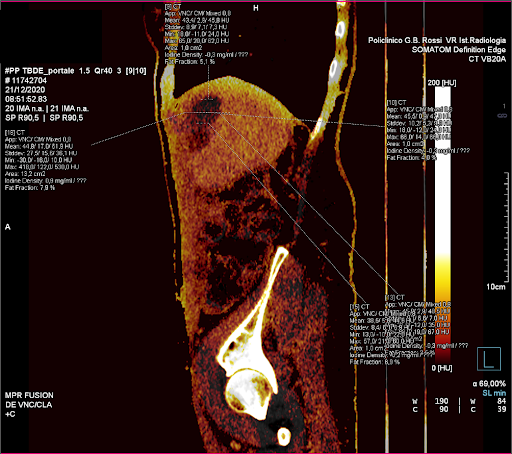

image

FIGURA 5. Esempio di analisi VNC con mappa dello iodio. Sono visibili le ROI di 1 cm2 tracciate manualmente sul piano assiale con i rispettivi valori ottenuti. Rispettivamente: la ROI superiore (A), tre ROI sul piano centrale (B-C-D), la ROI inferiore (E) e la ROI centrale con incluso un bordo di parenchima di 5mm (F).